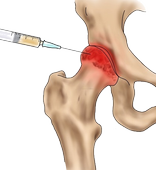

На месте осуществляется забор крови, введение лекарственных препаратов с помощью капельниц и инъекций.